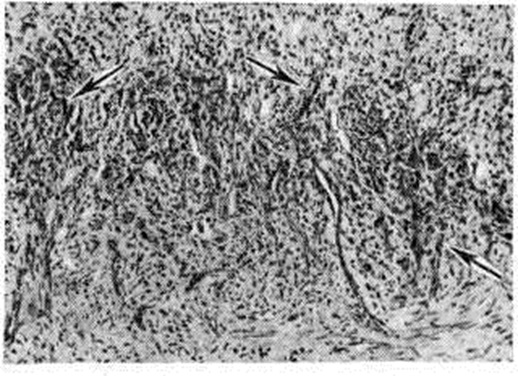

Микроскопически в опухоли всегда обнаруживают большое количество кровеносных сосудов, чаще капиллярного типа. Эндотелиальные клетки сочные, набухшие, местами сгруппированы в небольшие тяжи; вокруг сосудов — неспецифический воспалительный инфильтрат, состоящий из лимфоцитов, гистиоцитов, плазматических клеток и другие. На отдельных участках эндотелиальные клетки с явлениями атипизма и единичными фигурами деления ядер; встречаются разрастания веретенообразных клеток, среди которых видны сосудистые щели. В пределах опухоли определяются также участки грануляционной ткани различной степени зрелости (рисунок 2), некрозы, массивные кровоизлияния и скопления гемосидерина. Характерны связанные с сосудами пучки веретенообразных клеток, не полностью сформированные сосуды, нарушение целостности стенок и кровоизлияния вокруг сосудов (рисунок 3). В опухоли обнаруживают все указанные структуры в различных сочетаниях, что и создаёт разнообразие гистологический картины. Выделяют воспалительно-гранулематозную и позднюю опухолевую стадии развития Капоши саркома множественная геморрагическая.

В воспалительно-гранулематозной стадии отмечают большое количество расширенных кровеносных сосудов в дерме, эндотелий их набухший, сочный; вокруг сосудов — инфильтрация из лимфоидных элементов, плазматических клеток, гистиоцитов, фибробластов.

|

Характерной гистологический особенностью является наличие в соединительной ткани эндотелиальных клеток, из которых образуются новые сосуды, а также эритроцитов вне просвета сосудов и увеличение содержания гемосидерина. В ранних стадиях гистологический картина не всегда характерна: Капоши саркома множественная геморрагическая трудно дифференцировать от ангиомы и богатой сосудами грануляционной ткани. Правильному диагнозу помогает обнаружение в гранулематозной ткани экстравазатов и гемосидерина.

Поздняя опухолевая стадия (рисунок 4) характеризуется пролиферацией веретенообразных клеток различной формы — длинных, коротких, с изменёнными и часто палочковидными гиперхромными ядрами. Клетки располагаются в виде пучков, окрашивающихся пикрофуксином в розовато-красный цвет. Многие авторы относят их к мезенхимальным ангиобластическим элементам. Встречаются немногочисленные митотические фигуры. Участки подобного строения весьма напоминают картину фибросаркомы, отличаясь от неё наличием экстравазатов и зёрнышек гемосидерина. На других участках имеется большое количество сосудистых щелей, происходит интенсивная пролиферация сосудов и развивается соединительная ткань различной степени зрелости; число экстравазатов резко возрастает, образование гемосидерина более выражено. Взгляды на происхождение веретенообразных клеток при Капоши саркома множественная геморрагическая различны. Их относят к фибробластам, клеткам эндотелия, ретикулярным клеткам, нейромиодермальным и мезенхимальным элементам. На основании гистологический и гистохимические данных можно предположить, что источником роста является ангиобластическая мезенхима, и опухоль, по-видимому, развивается из незрелых мезенхимных перицитарных эмбриональных сосудистых клеток. Одни авторы считают, что новообразование связано с пролиферацией гладкомышечных элементов, другие предполагают его нейрососудистое происхождение. Есть основания полагать, что Капоши саркома множественная геморрагическая является системным первично множественным ангиолейомиоматозом, гистогенетически связанным с гладкомышечными элементами клеток мелких сосудов мышечного типа.